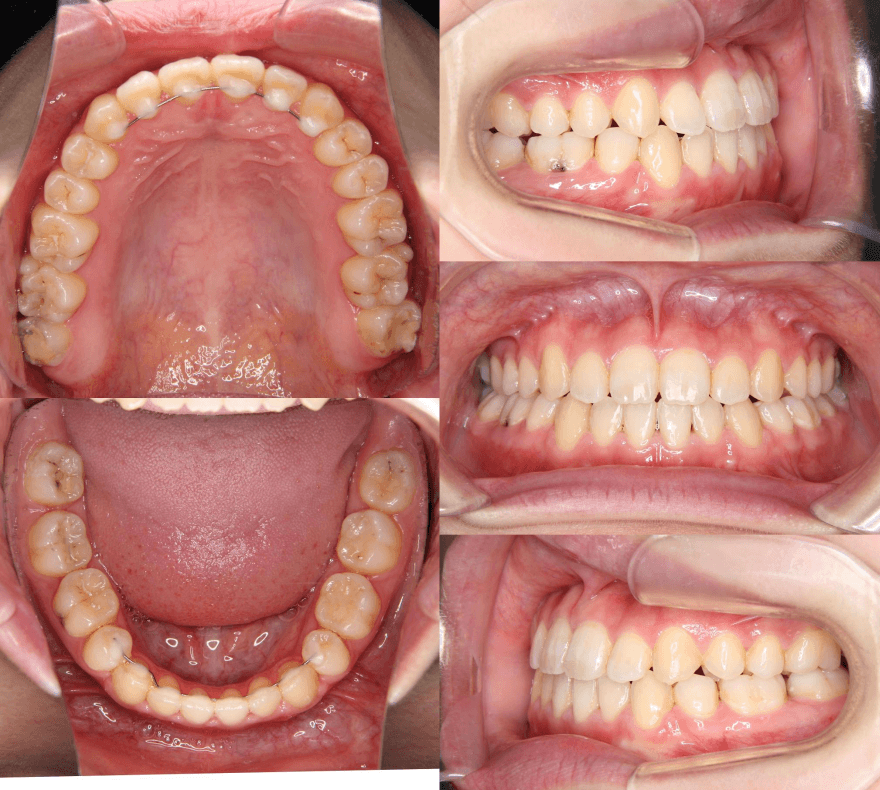

咬み合わせが逆であること(反対咬合)が気になる

| 年齢・性別 | 15歳 女性 |

|---|---|

| 主訴 | 咬み合わせが逆であること(反対咬合)を気にされて来院された女性。見た目や機能面の改善を希望されていました。 |

| 治療期間・回数 | 4年4ヶ月・28回 |

| 費用 | 900,000円 |